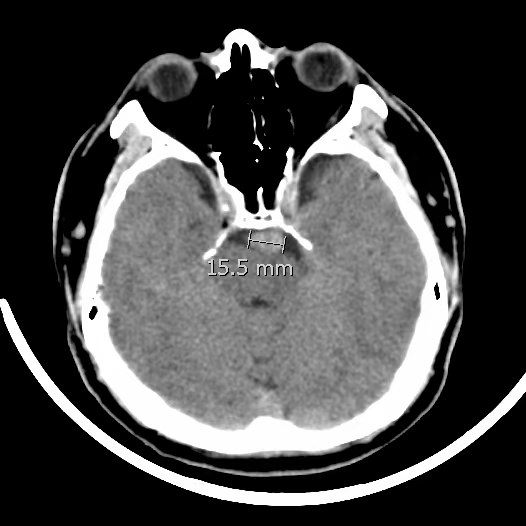

椎基底动脉冗长扩张症,是最棘手最复杂的脑血管病之一。患者从外地千里迢迢(3900余公里,仅高铁41小时)赶来东方医院诊治,期间症状不断加重(图2非真实大小)。术后一周复查:1、右侧肢体肌力明显改善;2、右侧肢体和枕部麻木症状明显改善;3、饮水呛咳缓解;4、共济失调明显改善;5、流涎消失;6、消失的味觉再次恢复。术后一周复查:血管修复良好(图5)。期待患者早日康复,早日奔赴工作岗位,保一方平安。